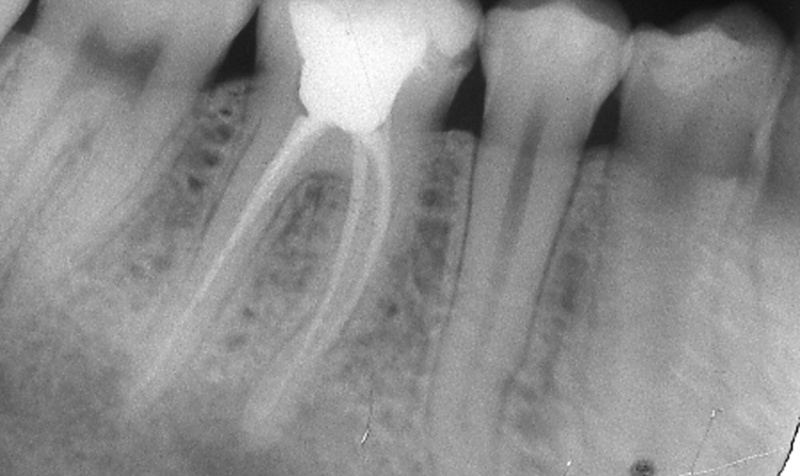

Endodontic treatments (Root Canals) consist in the curing conditions that affect the internal part of the tooth or pulp.

For example after a tooth fracture, a deep cavity or after removing a restoration; the internal tissue of the tooth can become inflamed or infected provoking an intense tooth pain.

In these cases, the affected tooth can require a root canal, which is a procedure that is realized in one session and relieves the pain and inflammation.